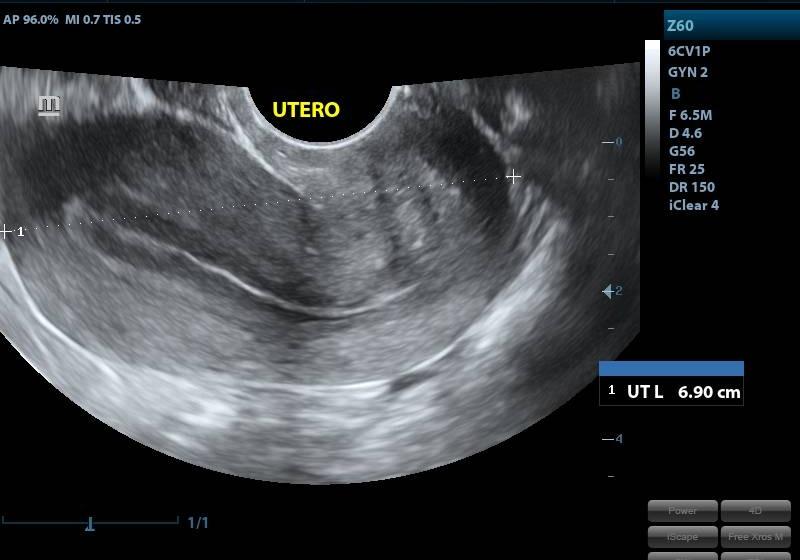

ECOGRAFIA ENDOVAGINAL

CONDICIÓNNO REQUIERE PREPARACION PREVIA

TIEMPO20 MINUTOS

TIPO RESULTADOSIMAGENES ECOGRAFICAS

ESPECIFICACIONESSE ESTUDIA: UTERO ANEXOS OVARIOS IMPLANTACION SACO GESTACIONAL VESICULA VITELINA LONGITUD DE EMBRION (LCC) PRESENCIA DE LATIDOS CARDIACOS OBSERVACION REACCION CORIODECIDUAL, DESCARTAR: HEMATOMAS. MIOMAS QUISTES TUMARACION